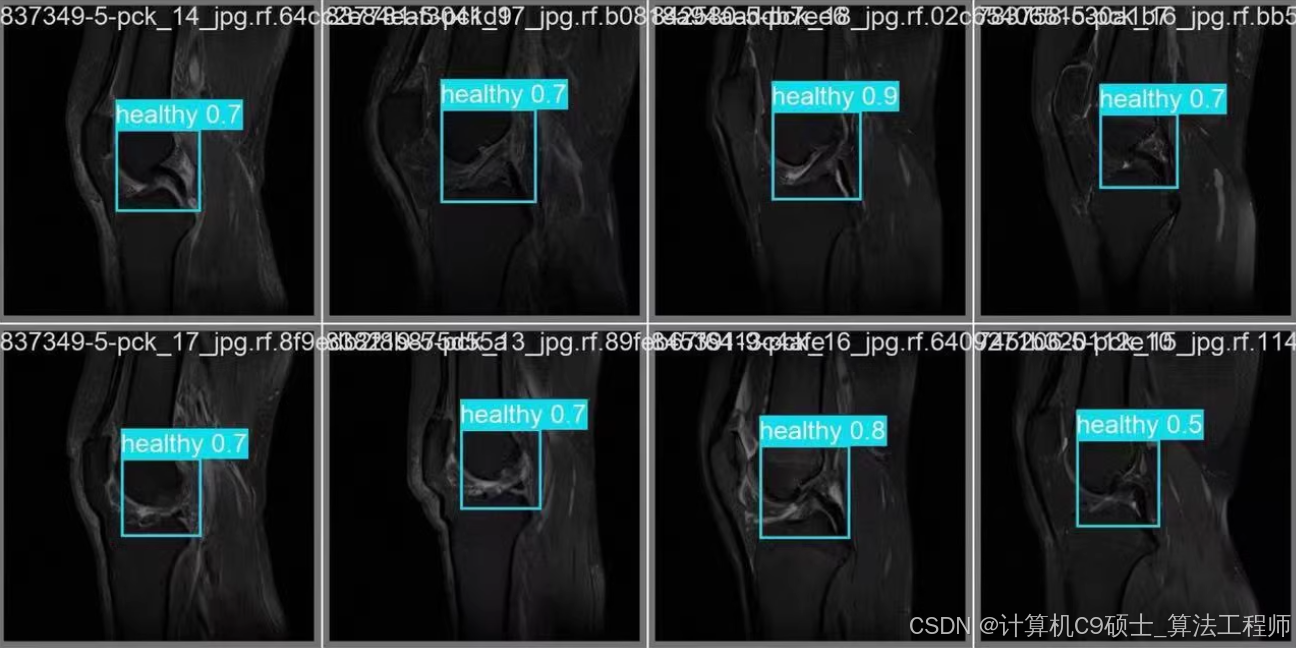

8. 可视化预测结果

使用以下Python代码来可视化模型的预测结果。

import torch

import cv2

import numpy as np

import matplotlib.pyplot as plt

# 加载模型

model = torch.hub.load('ultralytics/yolov5', 'custom', path='runs/detect/train/weights/best.pt')

# 读取图像

image_path = 'knee_injury_dataset/images/val/0001.jpg'

image = cv2.imread(image_path)

image = cv2.cvtColor(image, cv2.COLOR_BGR2RGB)

# 进行预测

results = model(image)

# 绘制预测结果

results.print()

results.show()